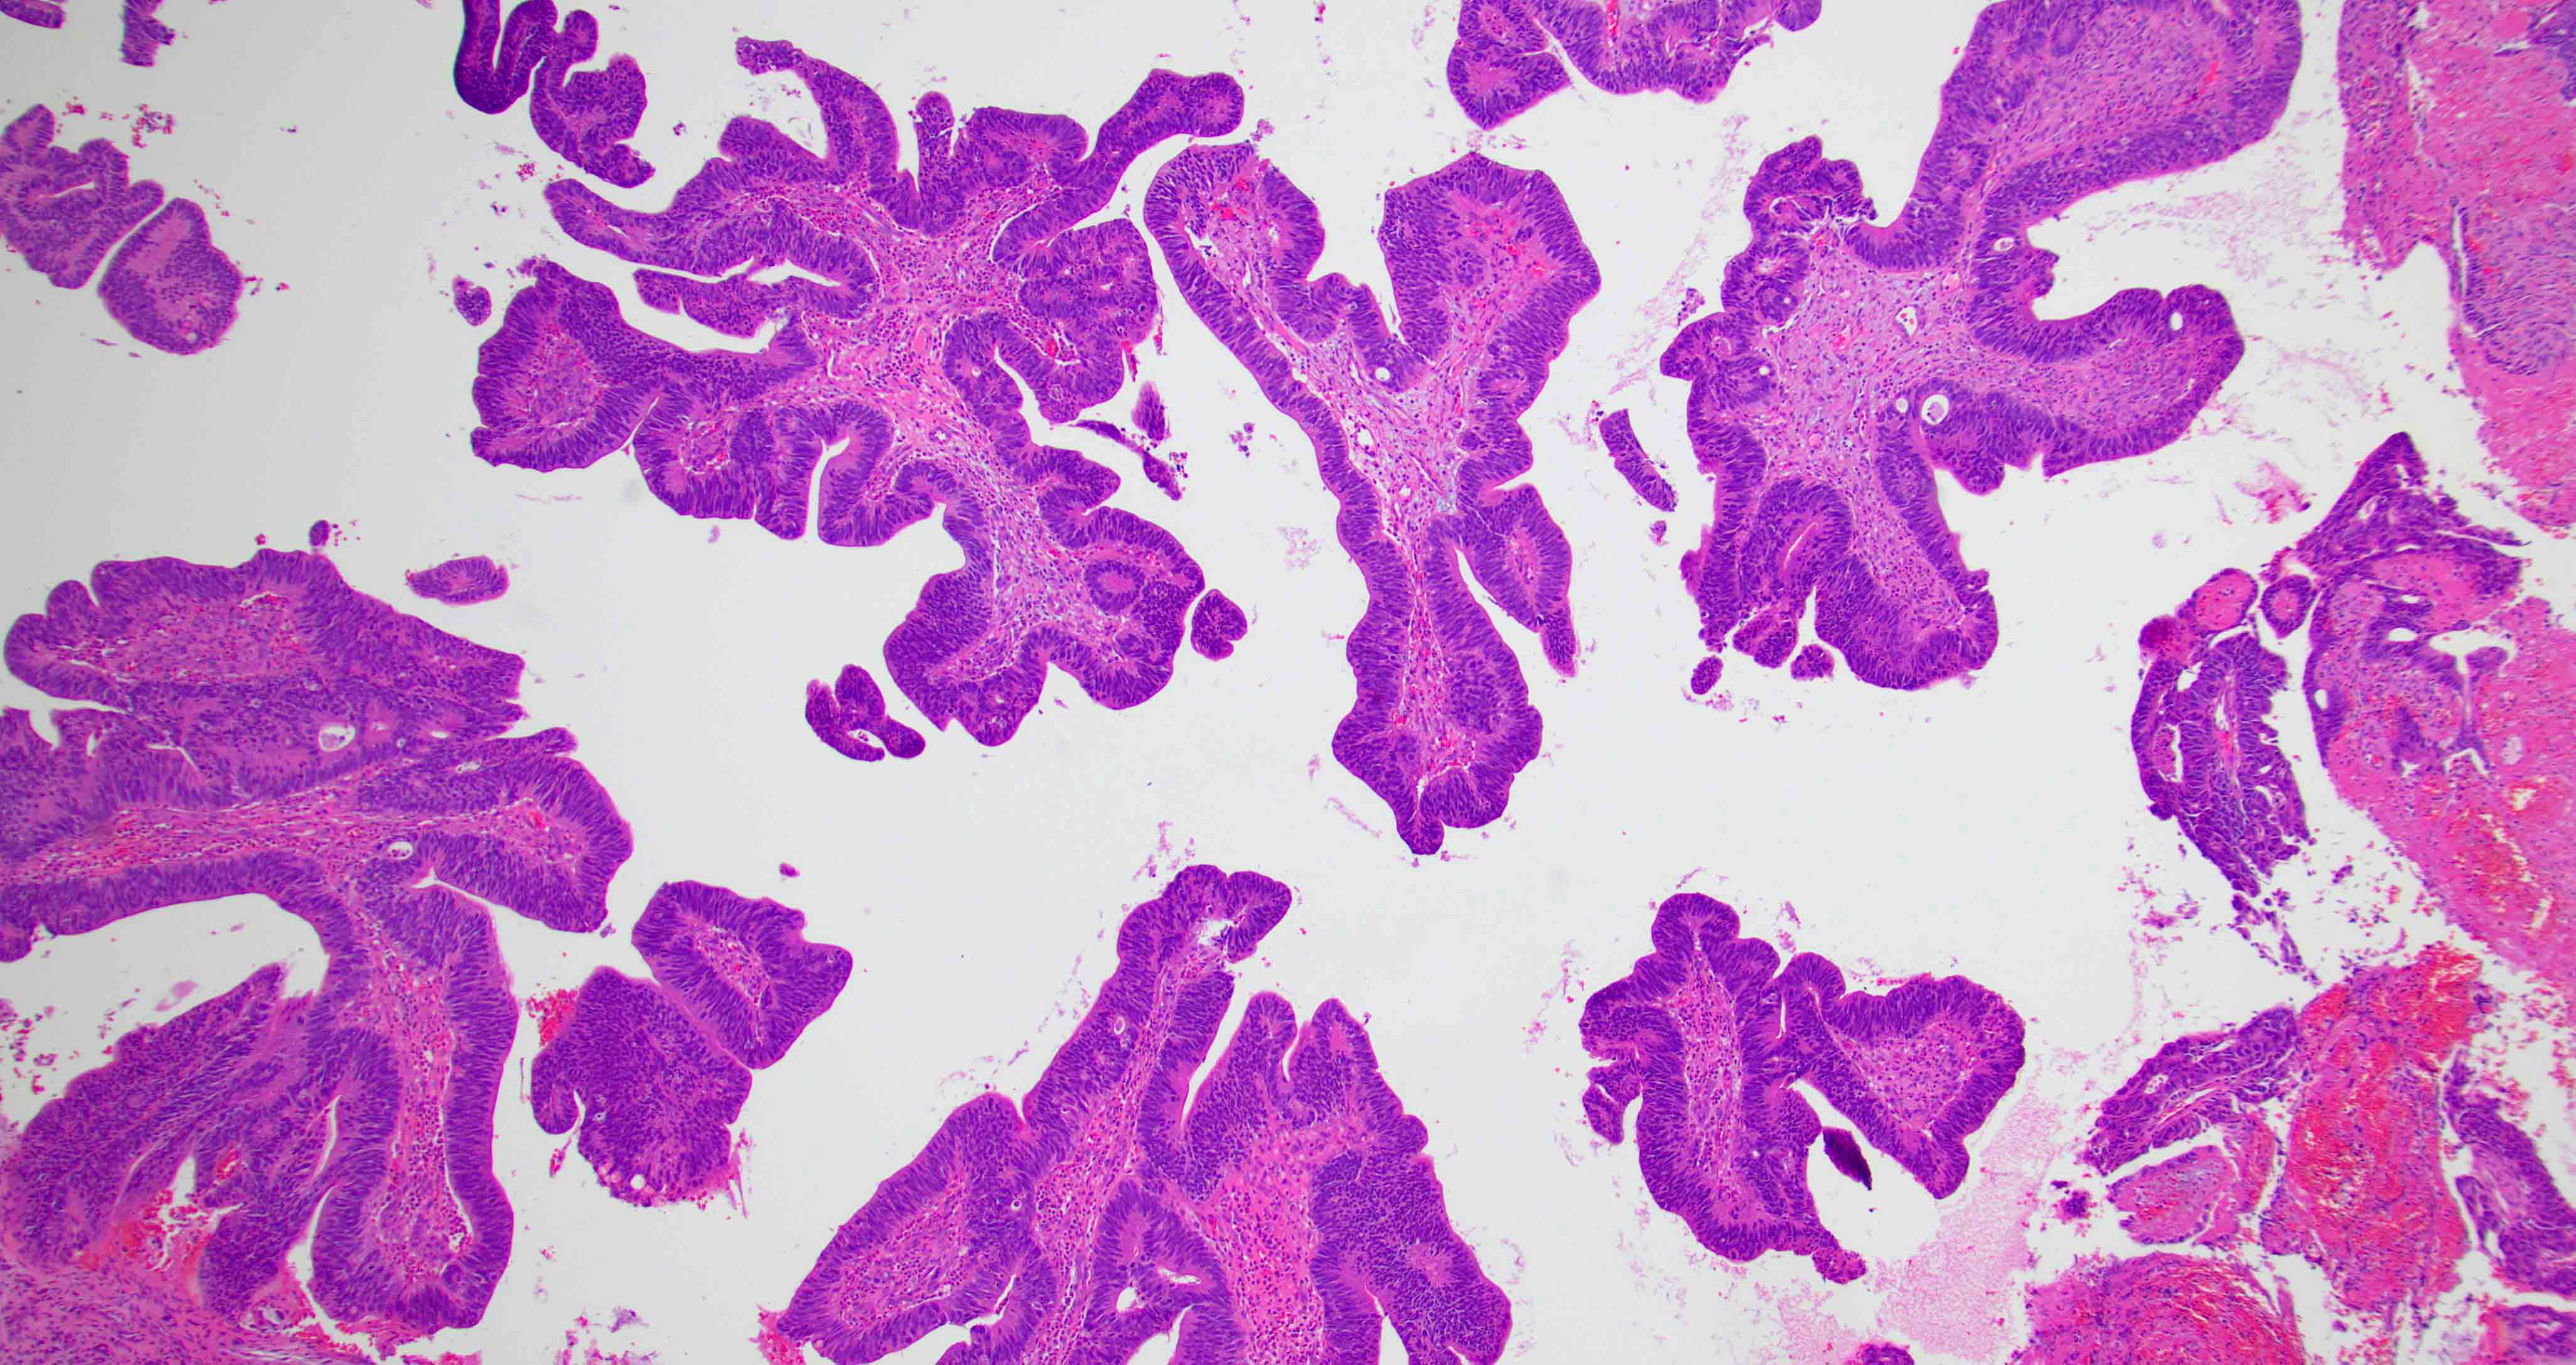

Microscopic (histologic) images

Contributed by Diana Bell, M.D.

Nonintestinal adenocarcinoma (non-ITAC)

- Low grade non-ITAC can exhibit exophytic papillae, tubular or glandular, trabecular, cribriform, clear cell and mucinous patterns

- Papillae and glands are usually lined by a single layer of uniform columnar or cuboidal cells with eosinophilic cytoplasm and slight cytologic aberrations